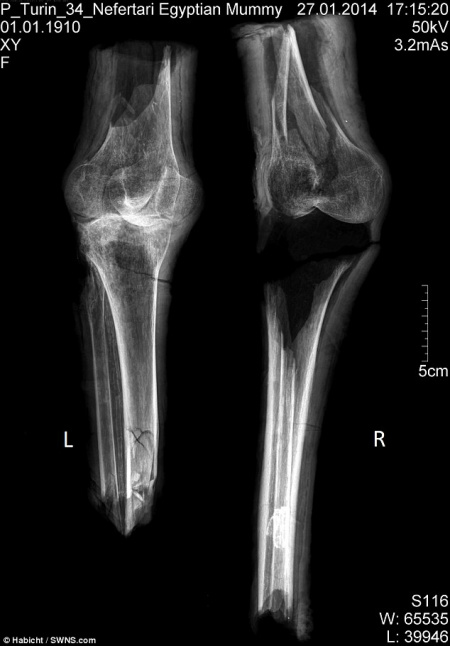

Especialistas encontraram um par de pernas em uma tumba egípcia e finalmente parecem ter descoberto sua origem. Encontrados durante escavações no Vale das Rainhas há mais de um século, os membros mumificados ficaram guardados em um museu de Turim.

Os arqueólogos que analisam os restos com mais de 3.000 anos, acreditam que eles poderiam pertencer à rainha Nefertari, esposa do faraó Ramsés, o Grande. Em 1904, arqueólogos italianos escavaram o túmulo da rainha Nefertari – considerada a esposa favorita de Ramsés II, mais poderoso faraó do Império. Entre as ruínas da tumba saqueada, eles recuperaram três pernas mumificadas.

Mas uma nova análise realizada por uma equipe internacional, incluindo pesquisadores da Universidade de York, usou técnicas científicas modernas para confirmar a identidade das pernas. Os investigadores concluíram que as pernas pertencem a uma mulher de meia-idade, que media cerca de 1,65 m de altura que pode ter tido artrite.

Segundo especialistas, a pessoa devia ter entre 40 e 60 anos quando morreu – mesma faixa etária de Nefertari. De acordo com um artigo publicado pela revista PLoS ONE, “’o cenário mais provável é que os joelhos mumificados realmente pertençam à rainha Nefertari”, afirmam os cientistas.

Usando análises químicas, datação por radiocarbono e análise de DNA, eles descobriram que o bálsamo usado no processo de mumificação condizia com o utilizado durante o reinado de Ramsés. As evidências sugerem que as pernas pertencem à Nefertari e não a suas filhas – que foram enterradas no mesmo túmulo.

“Nós só podemos supor que ladrões de tumbas tenham separado o corpo dos cadáveres enquanto procuraram amuletos de ouro e prata dentro dos invólucros. Pensamos isso porque só os joelhos mumificados sobreviveram. O resto do seu corpo permanece um mistério”, disse Fletcher.